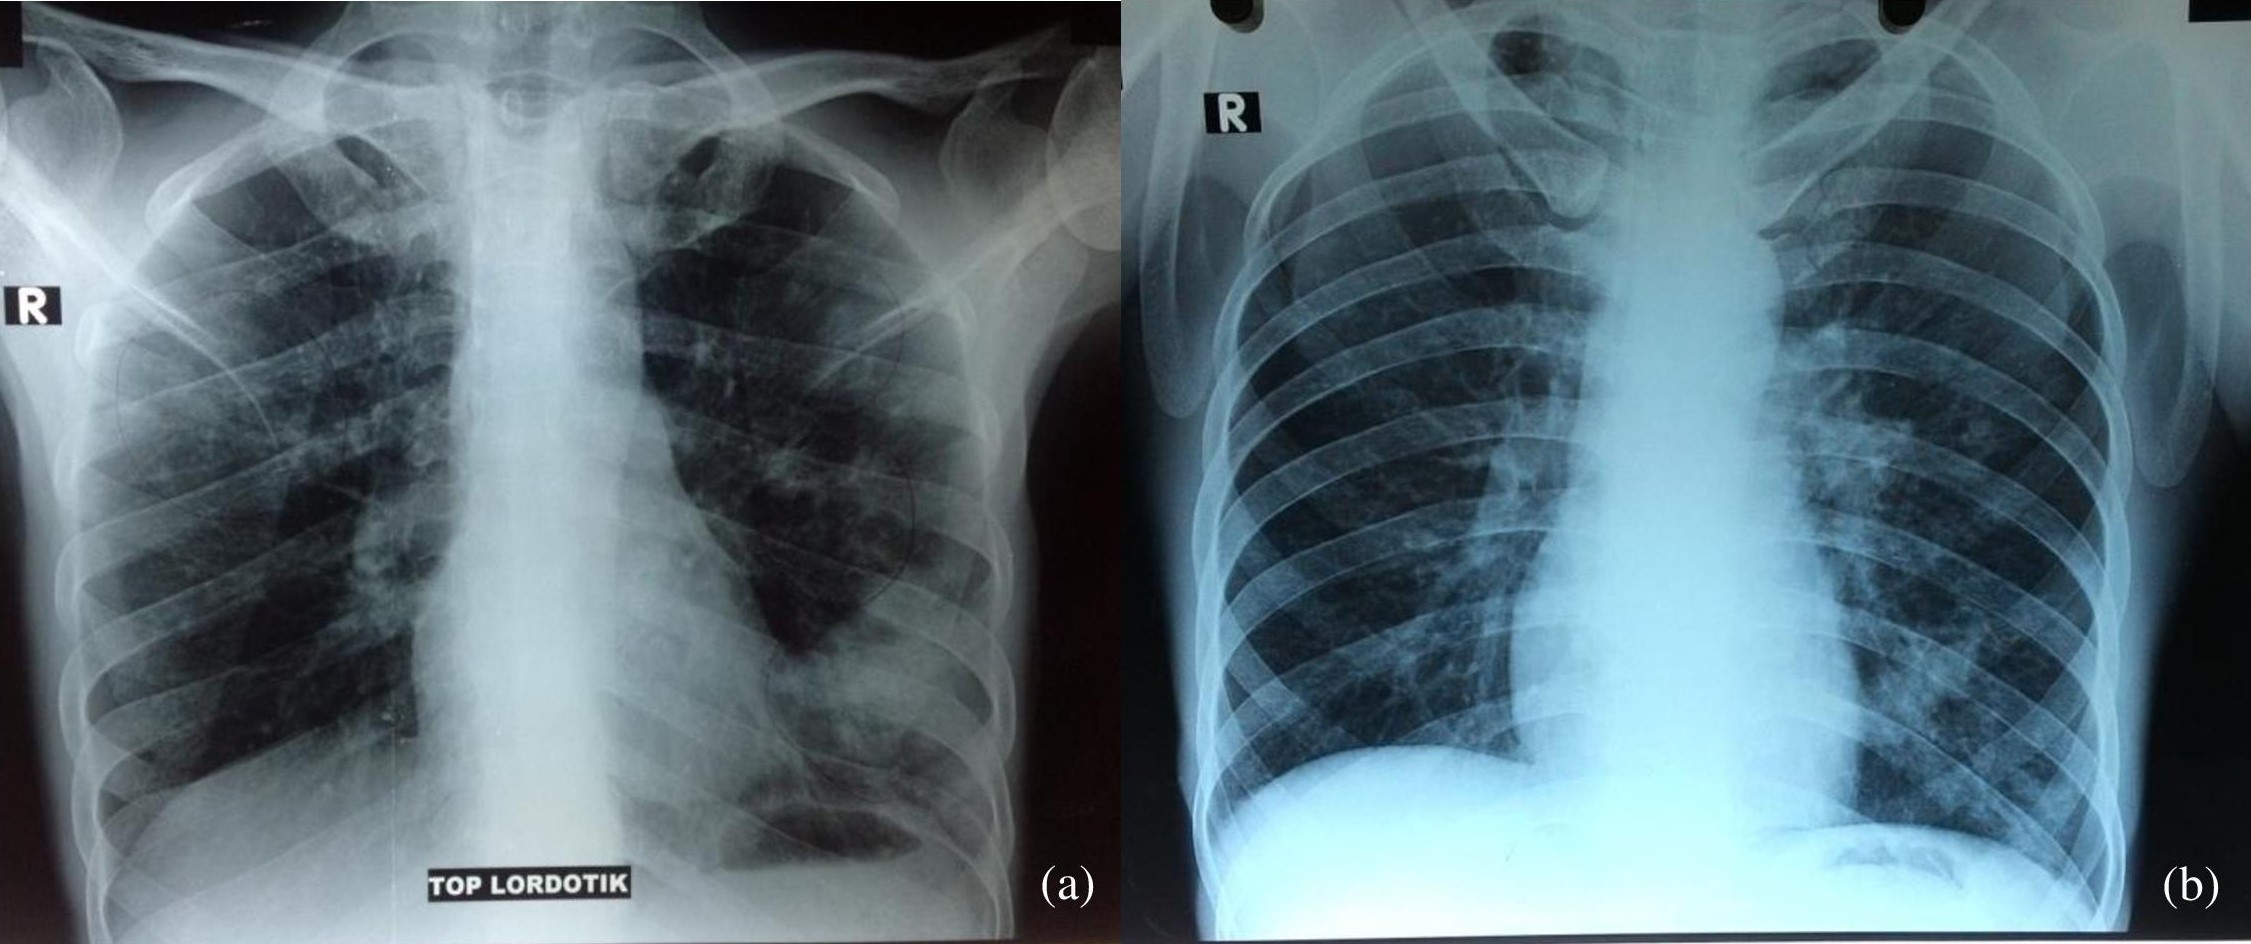

Chest Radiographs A Apicolordotic View Revealed Fibrotic Infiltrates Download Scientific Diagram

Chest Radiographs A Apicolordotic View Revealed Fibrotic Infiltrates Download Scientific Diagram from www.researchgate.net

Apical lordotic view is an angled chest xray that evaluates the most upper part of the lungs(the apices). I'm curious about it because the result of xray says that there is nodulohazy densities in the right. How many people will receive an allocation if everyone purchases at the maximum purchase limit? Apico means akwa ibom property and investment company. Lordotic view, apico lordotic view. September 10, 2010 @ 8:13 am · filed by mark liberman under phonetics and i meant for that to be a link to her youtube channel, but it has apparently been filtered: An apicolordotic view is an additional view of the lungs usually. Yeah ek special case hai chest ka, jisme app ko chest k.

Yeah ek special case hai chest ka, jisme app ko chest k. I am worried about my sister condition. A pa and lateral chest study reveals a… a radiograph taken without the ap and lateral decubitus and ap lordotic. Find out all about lordotic : Though there are ways to perform exercises wrong, meaning that it would reinforce the. Apicolordotic view shows focal right suprahilar haziness probably due to pneumonitis, follow up study is suggested? What is qredo built on? Apico means akwa ibom property and investment company. These examples have been automatically selected and may contain sensitive content.read what is brain fog anyway? Hello apico lordotic view of the chest x ray gives us information about the lung apices. Articulated with the apex of the tongue touching or near the alveolar ridge , as ( t ), (. Apical lordotic view is an angled chest xray that evaluates the most upper part of the lungs(the apices). Meaning, pronunciation, translations and examples.